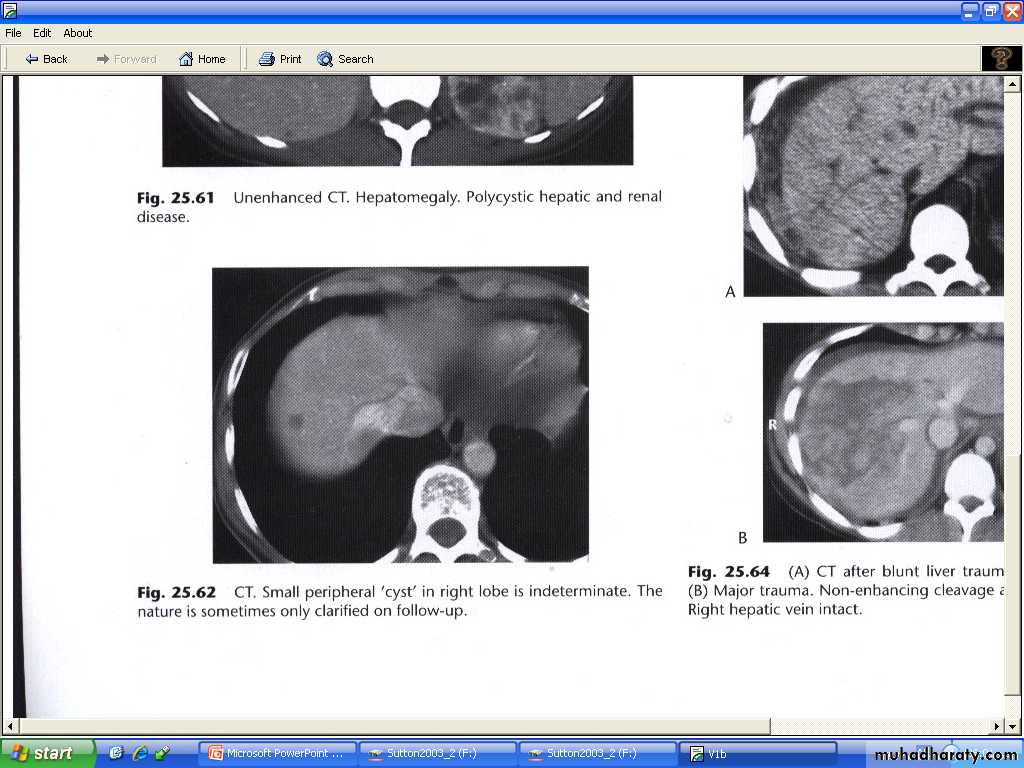

# single or multiple , usually congenital , some due to infection.

# multiple hepatic cysts occur in polycystic disease ( not only affect the kidney but may also affect the liver and other organs )

# at US : typical features of cysts elsewhere ( sharp margin , no echo within the lesion "anechoic", intense echo from the front and back walls with acoustic enhancement deep to the larger cysts.

# at CT : very well defined margins , attenuation value similar to that of water (HU=0-15 ). Its often not possible to characterize small lesions and with lesions below 1 cm in diameter its almost never possible to distinguish cyst from neoplasm.

Liver trauma :

Is the commonest abdominal injury that leads to death.Features are : parenchymal lacerations , subcapsular and intrahepatic haematomas.

Lacerations and haematomas are recognized as low density areas relative to the contrast enhanced parenchyma , leakage of contrast indicate active bleeding .

Although US and MRI can demonstrate liver injury , CT is the best technique, which can survey other organs like spleen and kidneys. And identify any peritoneal fluid collection.